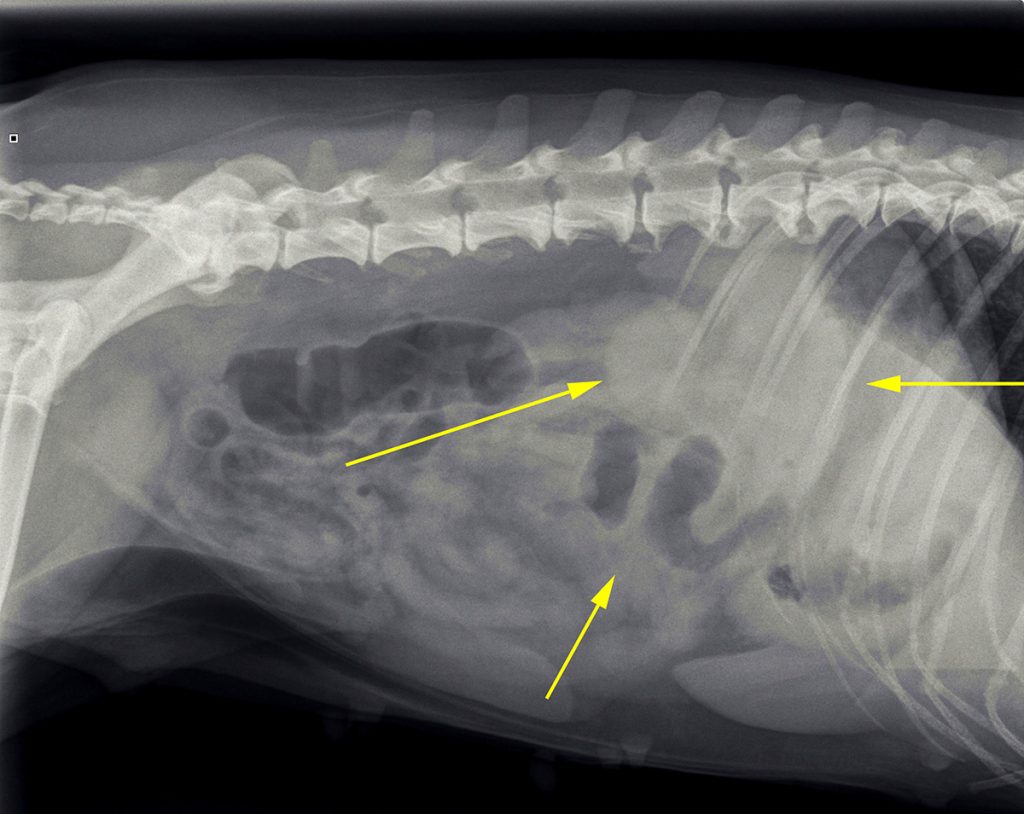

Op basis van deze afwijkingen is er toen voor gekozen om röntgenfoto’s te maken.

De belangrijkste afwijkingen die op de röntgenfoto’s te zien waren: minder contrast dan we gebruikelijk zien en mogelijk een structuur. Er was echter geen aanwijzing voor een verstopping.